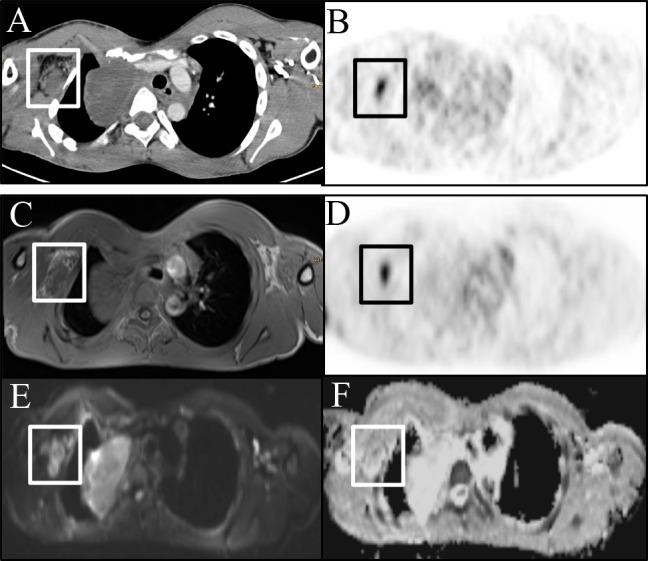

Patients diagnosed with neurofibromatosis type 1 and peripheral nerve sheath tumors (PNST) were enrolled in this prospective, IRB-approved study. After a single [F18]-FDG injection, patients consecutively underwent [F18]-FDG-PET/CT and [F18]-FDG-PET/MRI on the same day. Maximum and mean standardized uptake values (SUVmax, SUVmean) on [F18]-FDG-PET/CT and [F18]-FDG-PET/MRI were compared, and correlated with minimum and mean apparent diffusion coefficients (ADCmean, ADCmin).

A total of 12 (6 male/6 female, mean age was 16.2 ± 5.2 years) patients were prospectively included and analyzed on a per-lesion (n = 39) basis. The SUVmean of examined PNST showed a moderate negative correlation with the ADCmean (r = -.441) and ADCmin (r = -.477), which proved to be statistically significant (p = .005 and p = .002). The SUVmax of the respective lesions, however, showed a weaker negative correlation for ADCmean (r: -.311) and ADCmin (r: -.300) and did not reach statistical significance (p = .054 and p = .057). Lesion-based correlation between [F18]-FDG-PET/MRI and [F18]-FDG-PET/CT showed a moderate correlation for SUVmax (r = .353; p = .027) and a strong one for SUVmean (r = .879; p = .001)). Patient-based liver uptake (SUVmax and mean) of [F18]-FDG-PET/MRI and [F18]-FDG-PET/CT were strongly positively correlated (r = .827; p < .001 and r = .721; p < .001) but differed significantly (p < .001).

We found a statistically significant, negative correlation between glucose metabolism and cell density in PNST. Thus, ADCmean and ADCmin could possibly add complimentary information to the SUVmax and SUVmean and may serve as a potential determinant of malignant transformation of PNST.